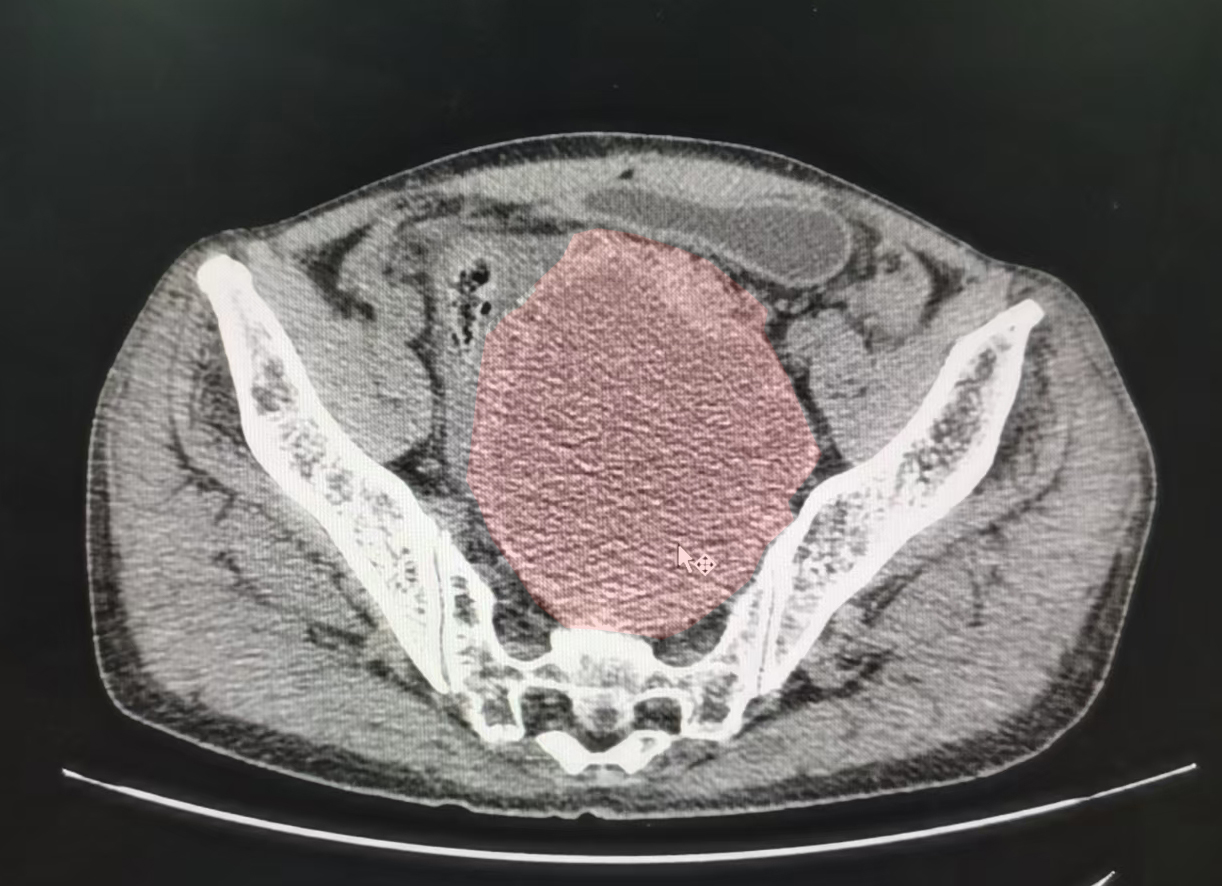

近日,在闫庆辉、张国建教授的指导下,我院普外三科(肛肠外科专业)林林团队运用腹腔镜微创手术技术,为一名盆腔巨大直肠间质瘤(GIST)患者完整切除了直径达15厘米的肿瘤,解除了患者因肿瘤压迫导致的排尿排便障碍...